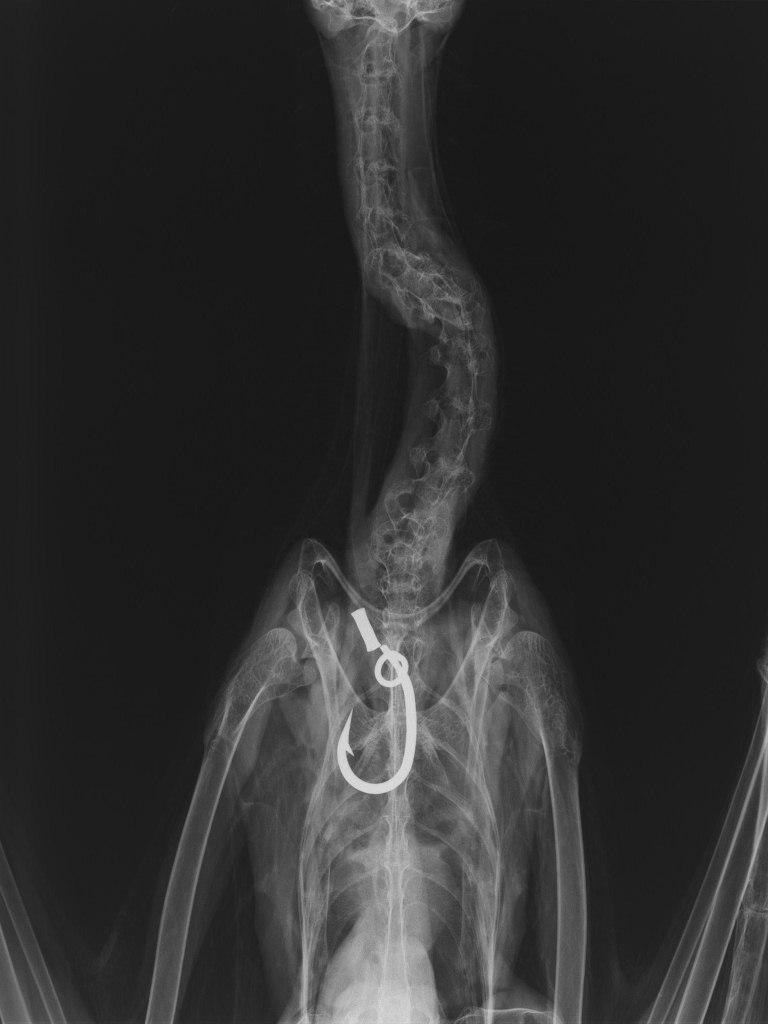

嘴から太い釣り糸が出ており、レントゲンを撮影してみると約5cmの釣り針を飲み込んでいました。

【レントゲン写真】